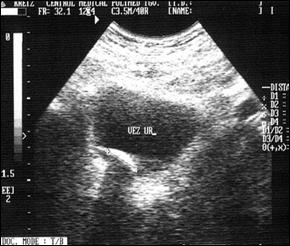

1. Diagnosticul diferential cu litiaza vezicala radiotransparenta

Ecografia vezicii urinare evidentiaza imagine hiperecogena, cu con de umbra posterioara (calcul)

Figura 54. Imagine radiotransparenta (2,5/1,8 cm, vizibila pe cistografie) |